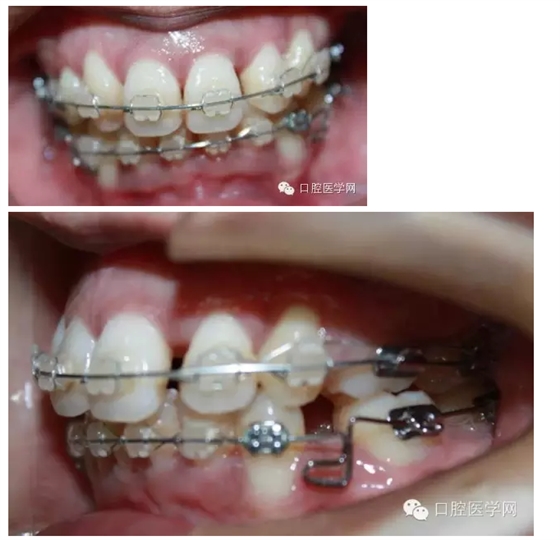

排齊后,我用搖椅方鈦絲壓低下前牙,結(jié)果一個(gè)月之后,牙齒基本上沒有什么變化,弓絲變得平直。之后再試了一次,也幾乎沒有效果。因?yàn)榛颊叩腟pee曲線太深了。

之后我換用0.018x0.025不銹鋼絲,在33,43遠(yuǎn)中彎制水平曲,階梯曲,結(jié)果3個(gè)月后,效果不明顯,而且牙齒變得有一些不整齊之后我再次用0.016x0.022niti絲,排了一下,在33,43的遠(yuǎn)中彎制后傾曲。

最后我用0.016x0.022不銹鋼絲,在33,43遠(yuǎn)中彎制水平曲,階梯曲和后傾曲,3個(gè)月后,深覆合明顯緩解。

這個(gè)病例花了9個(gè)月時(shí)間,才明顯壓低下前牙,打開咬合。這期間有很多值得我們思考的地方。